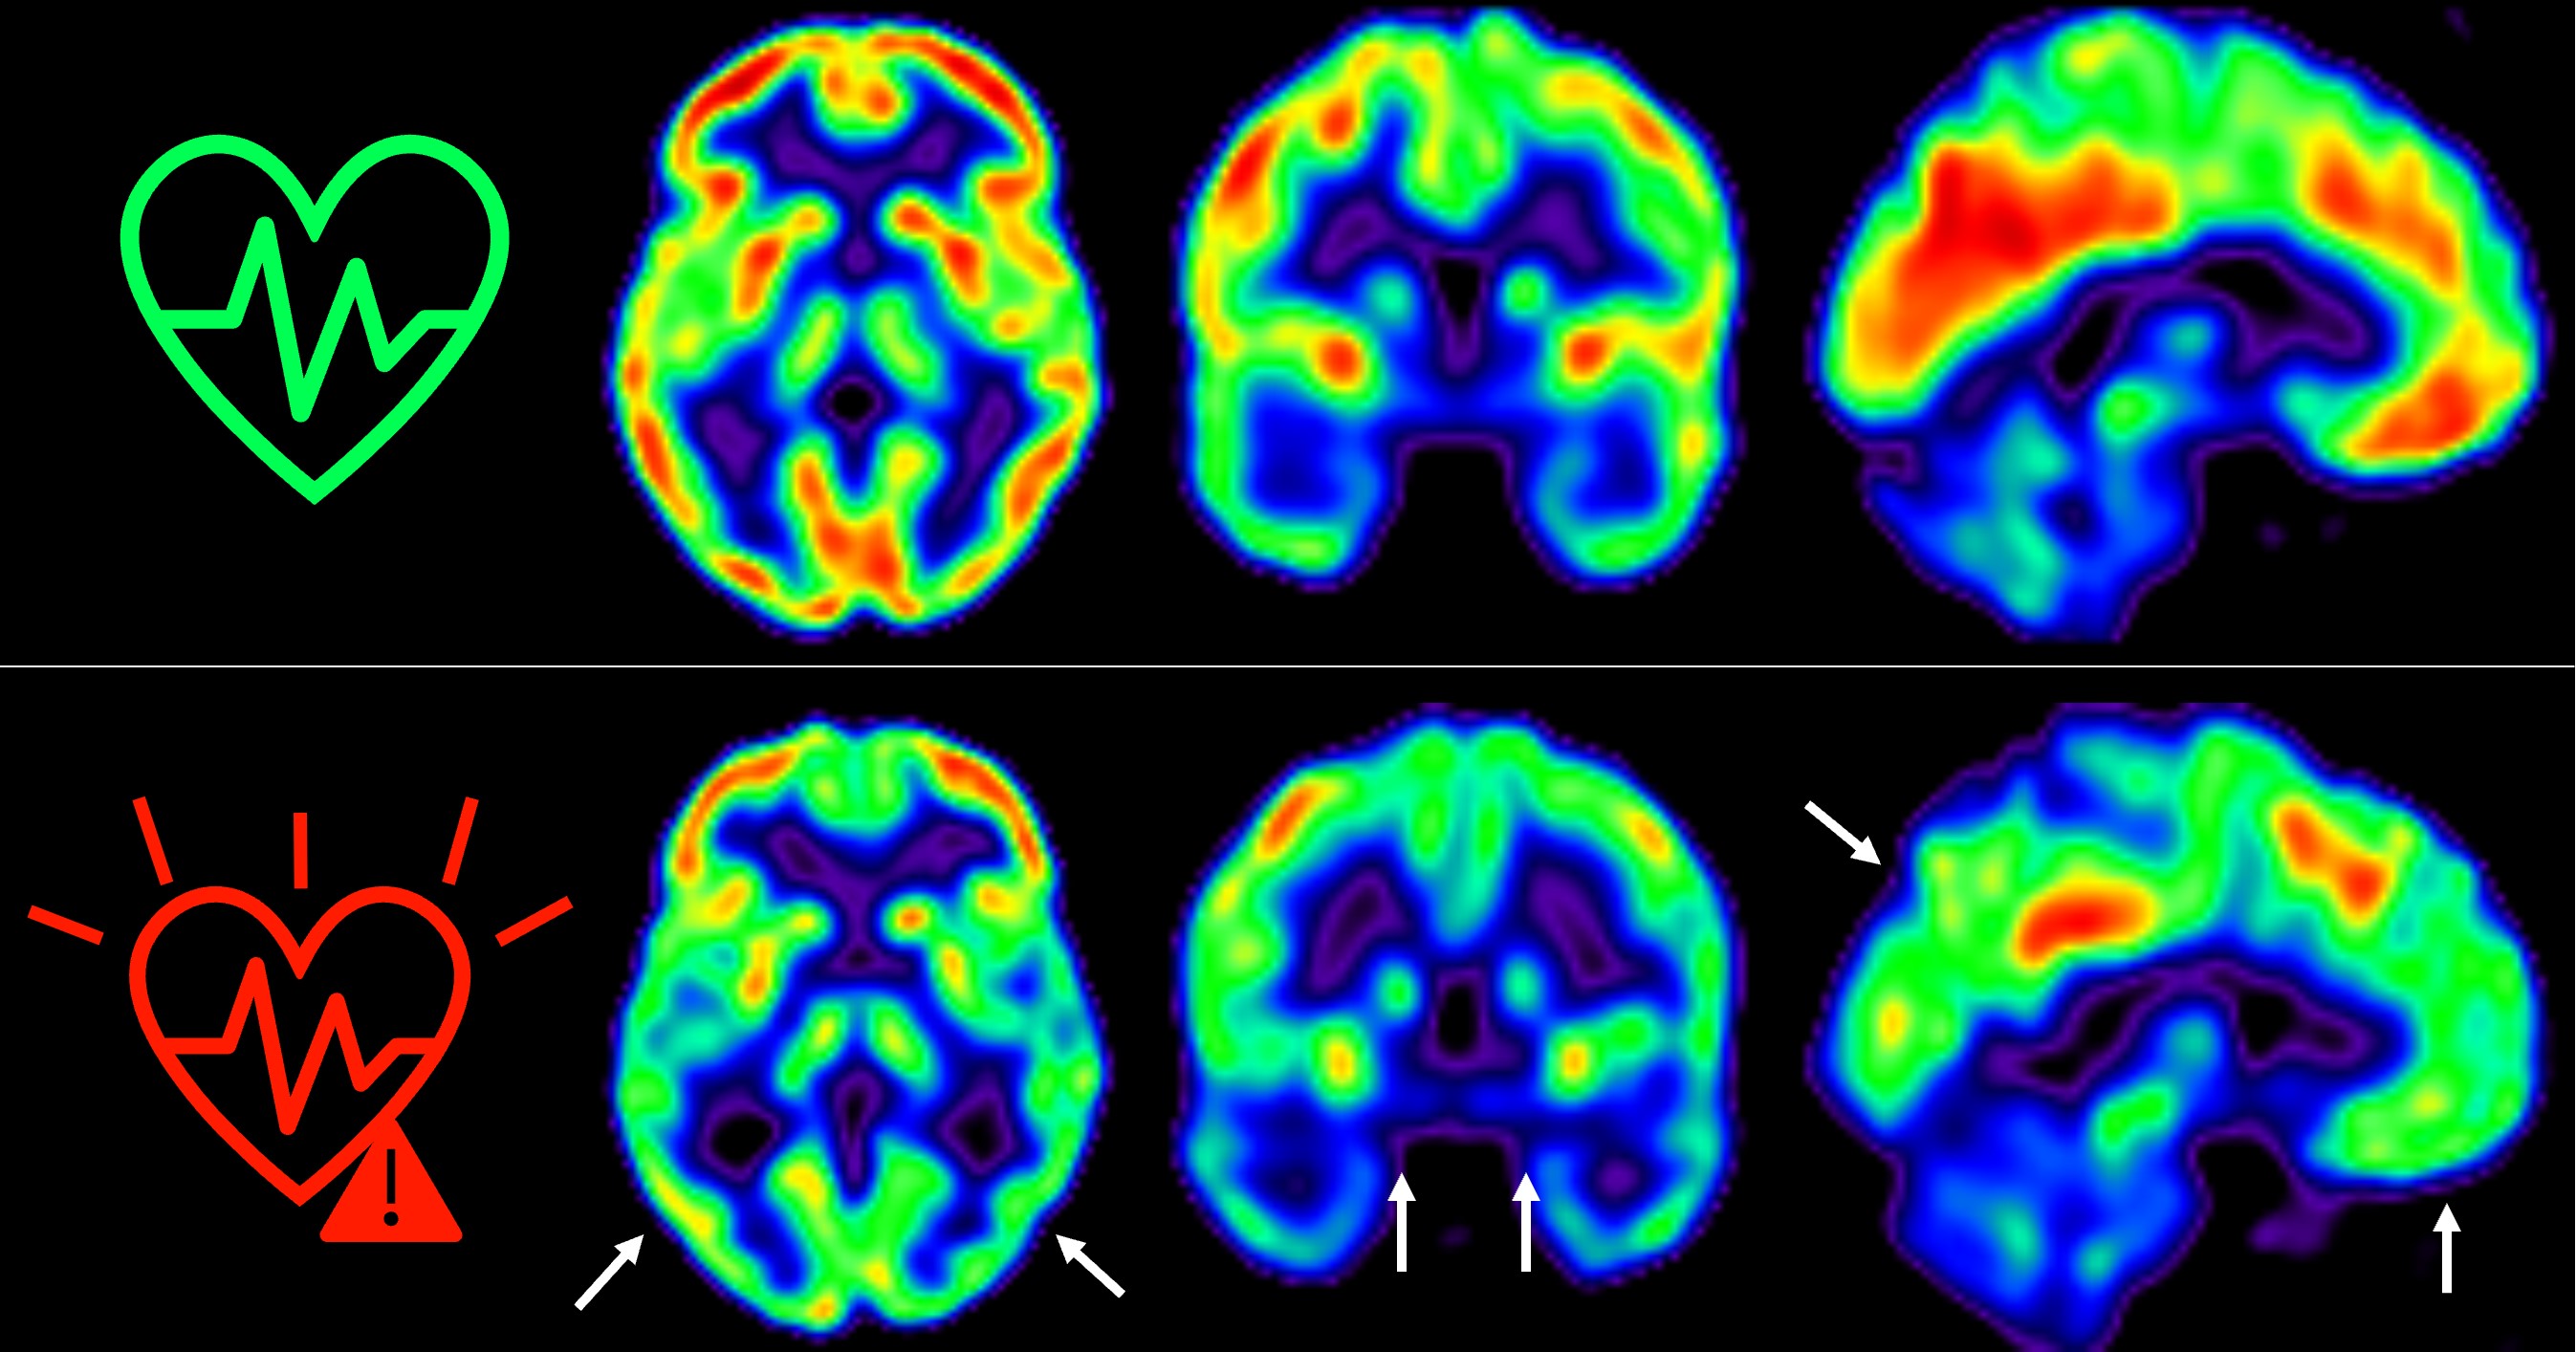

- Ictus isquémico o hemorrágico

- Hemorragia o derrame cerebral